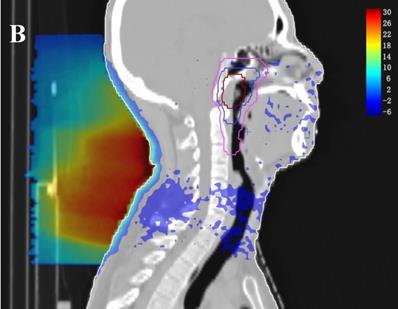

Dose difference distribution map (Plan+ - Plan-)

In the TPS, the results from two plans of the same patient can be directly subtracted to calculate the dose difference distribution map for the patient. As shown in Figure 3, the blue to red gradient represented different absolute dose difference values ranging from -6 Gy to 30 Gy. The dose distribution was dramatically altered due to the attenuation and bolus effect of the immobilization devices. In particular, as shown in B) and C), the neck dose near the head and neck immobilization device was significantly reduced, mainly due to the attenuation when the incident beam ray passes through the immobilization device. Changes in radiation scattering and build-up effect occurred due to the presence of low-density foam in the vacuum pad between the patient's neck and the floor plate. As a result, the dorsal neck skin dose was increased by approximately 10 Gy (Figure 3A, 3B).

Figure 3

Three dimensional dose difference distribution map for a typical NPC case. Dose difference was calculated through subtracting Plan- from Plan+. (A: Cross-sectional plane, B: Sagittal plane, and C: Coronal plane).

The establishment of a virtual model (including geometry and density information) for the treatment couch top within the TPS is a common method used to calculate the attenuation effect of the treatment couch on treatment planning [6,11,12]. In this study, we contoured the head and neck immobilization devices into the external body contour to calculate the immobilization device impact on the dose distribution of NPC IMRT. The density information of the immobilization devices showed the TPS calculation algorithm was able to compute dose for the situation with the immobilization devices enclosed. Due to the attenuation of the immobilization devices, CRs and Dmean in Plan+ were reduced compared to those in Plan- (the prescription dose coverage rates of the four targets were decreased by 1.5-9.9%, and the average doses were decreased by 0.9-1.9%). The attenuation effect was greater on the dose coverage rates of PTVnd and PTV2 (-9.9% and -3.6%, respectively), mainly because the two PTVs were spatially closer to the immobilization device. Table 1 showed that the Plan+ prescription dose coverage volumes for PTVnd and PTV2 were less than 95%, and according to the protocols of nasopharyngeal carcinoma IMRT planning in our center, these plans are not suitable for clinical treatment. Among the doses in OARs, except the near-maximum doses for the brain stem and spinal cord PRV had no significant difference, the average doses of all other OARs were statistically significantly reduced (with a maximum difference of 1.7%). Figure 2 showed a similar result; the DVH curves of the brain stem and spinal cord did not show significant differences between the two plans, but the curves for each PTV exhibited a certain degree of separation. The dose difference maps in Figure 3 also showed that due to the presence of the head and neck immobilization device, the dose distribution in the patient was reduced compared to that when the immobilization device was not considered. In particular, the dose in the portion of the lower neck that is close to the head and neck immobilization device was significantly reduced (most of which is in the PTVnd and PTV2 areas), mainly due to the attenuation effect of incident radiation passing through the immobilization device.